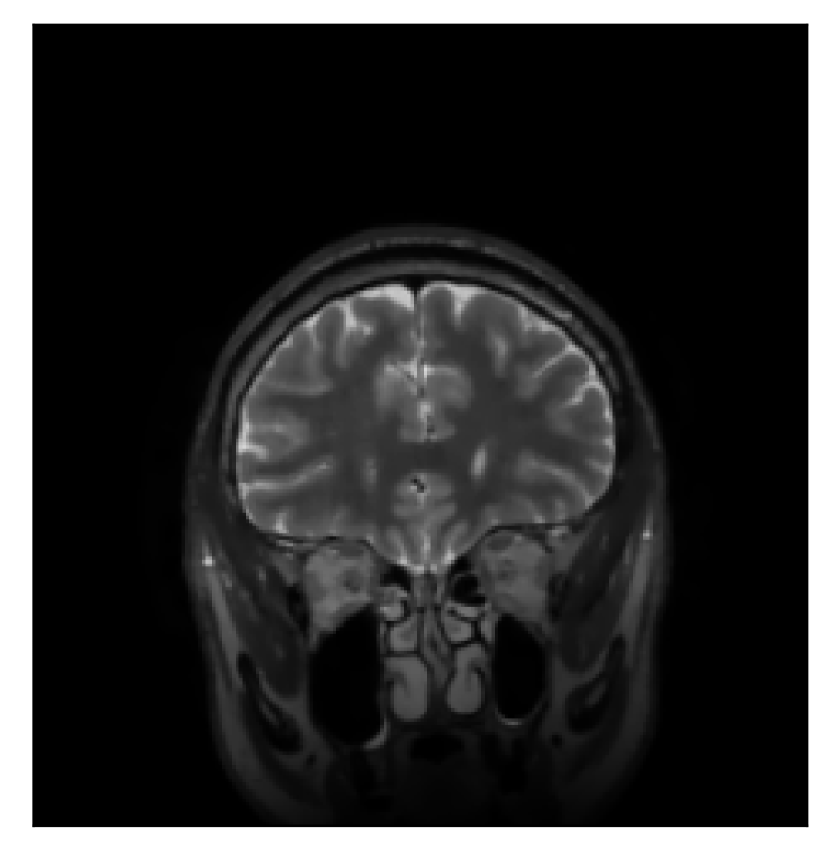

3.2 Experiment 2: on the choice of the reference contrast

This in-vivo experiment tests the proposed correction scheme with respect to a different combination of corrupted and reference contrast, namely a T1-weighted corrupted contrast with a T2-weighted reference contrast (see Table 1). For this experiment, we prompt volunteer 2 to move five times during the acquisition. The corrupted acquisition employs randomized sampling.

In Section 4.2, we gather the results for this experiment.

| Section 3.2, Figure 10 | Sagittal | 25.84 | 28.07 | 0.7032 | 0.8093 |

| Coronal | 26.35 | 30.40 | 0.7851 | 0.9021 | |

| Axial | 28.11 | 30.54 | 0.8248 | 0.9012 | |

The motion-corrected full-volume scans were analyzed by a neuroradiologist with 16 years of experience. These were generally deemed of good radiological quality. The motion-related artifacts have been completely removed, and the results are quite close to the ground truth. In Table 3, we organized a more detailed qualitative analysis of the 3D results, geared toward a radiological assessment of the corrected scans.

| Section 3.2, Figure 10 | T1 | Completely corrected | Some blurring | No additional artifacts | Good grey white matter differentiation, |

| some loss of grey matter low signal | |||||

4.2 Experiment 2: choice of the reference contrast

With the experiment described in Section 3.2, we demonstrate the flexibility of the correction scheme with respect to the choice of the reference contrast. The results are shown in Figure 10. Contrary to the experiments detailed in the previous section, we are now considering a T2-weighted reference contrast to guide the correction of a T1-weighted corrupted contrast. The quality of the correction indicates that the proposed technique is rather flexible in terms of reference contrast.

Sagittal

Coronal

Axial

Coronal detail